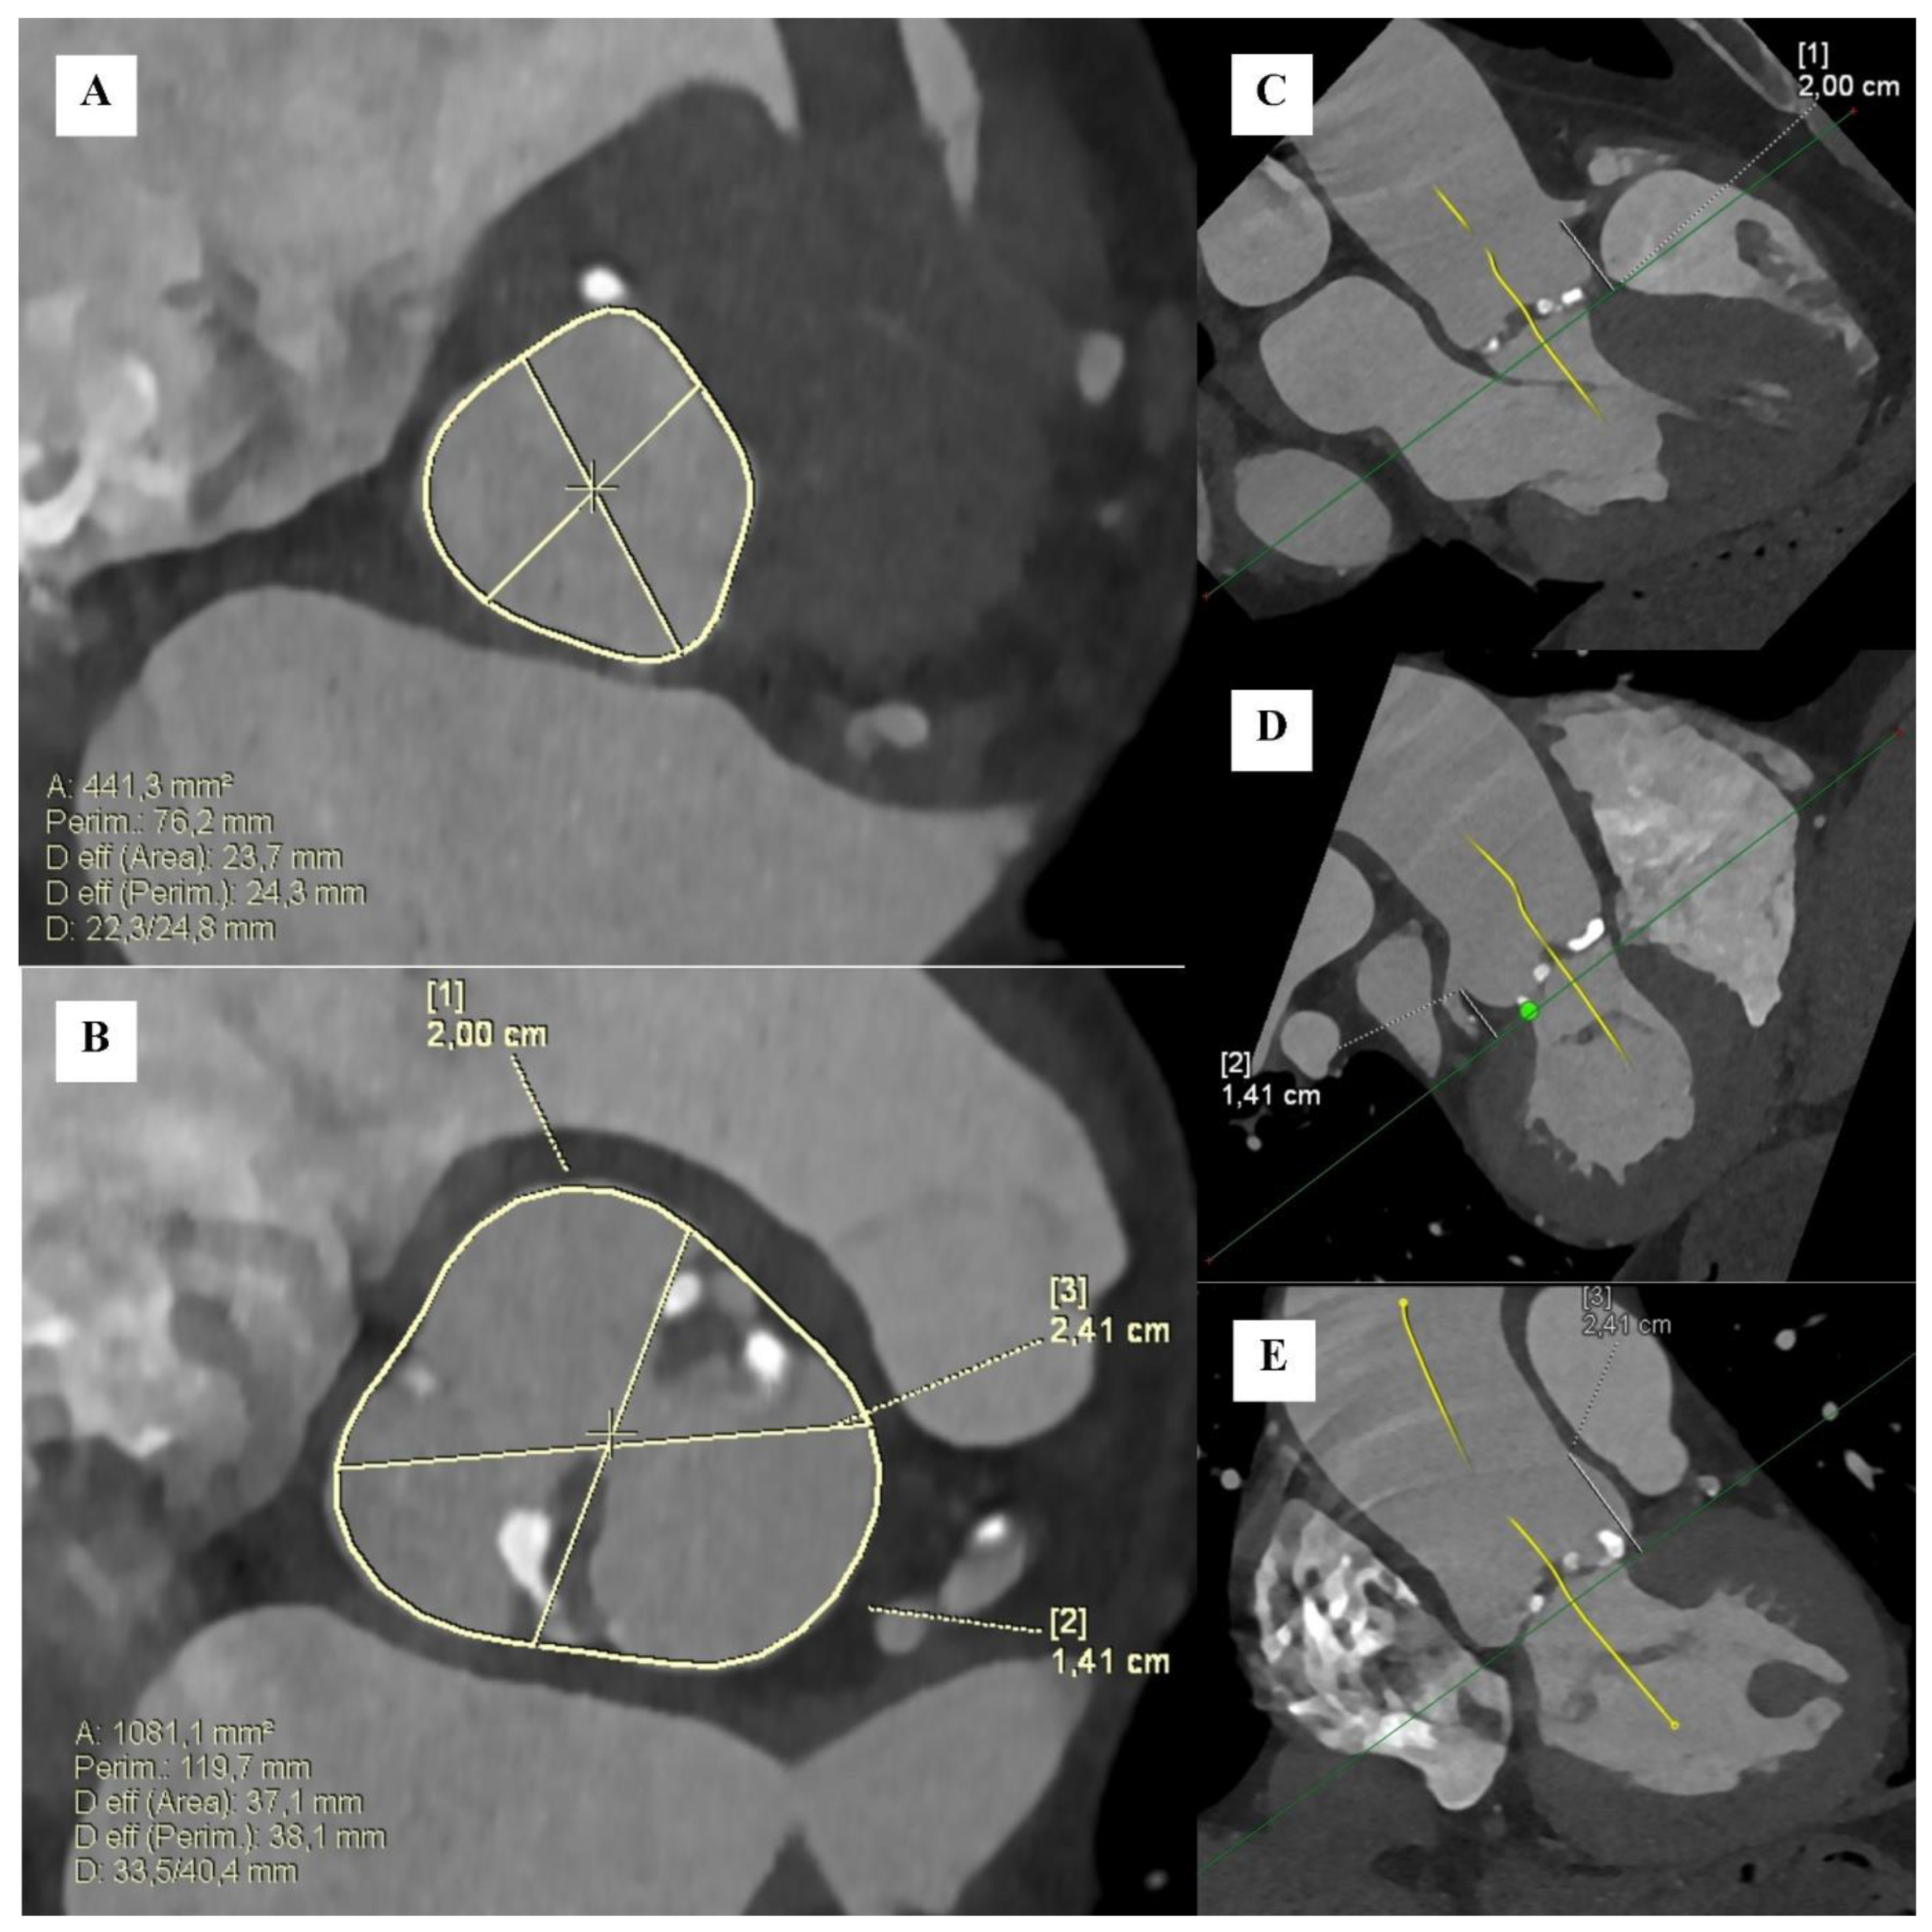

- Kim, W.K.; Renker, M.; Rolf, A.; Liebetrau, C.; Van Linden, A.; Arsalan, M.; Doss, M.; Rieck, J.; Opolski, M.P.; Mollmann, H.; et al. Accuracy of device landing zone calcium volume measurement with contrast-enhanced multidetector computed tomography. Int. J. Cardiol. 2018, 263, 171–176. [Google Scholar] [CrossRef]

- Angelillis, M.; Costa, G.; De Backer, O.; Mochi, V.; Christou, A.; Giannini, C.; Spontoni, P.; De Carlo, M.; Sondergaard, L.; Miccoli, M.; et al. Threshold for calcium volume evaluation in patients with aortic valve stenosis: Correlation with Agatston score. J. Cardiovasc. Med. 2021, 22, 496–502. [Google Scholar] [CrossRef] [PubMed]